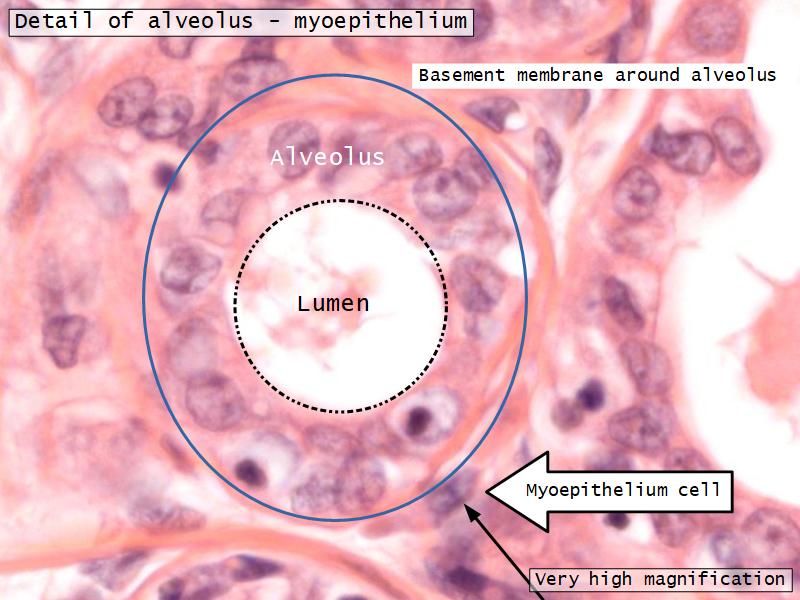

Mammary gland

Write short notes describing the structure of the mammary gland.

- Compound tubuloalveolar gland

Active gland

- Much larger than resting phase

- Terminal ducts proliferate to form alveoli

- Alveoli

- Surrounded by incomplete myoepithelial cells

Alveolar cells

- Apocrine secretion

- Active state

- Resting state